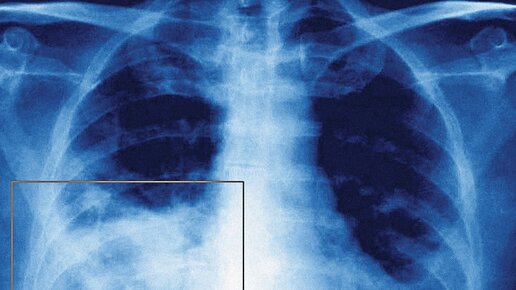

Двухсторонняя пневмония - что это

Пневмония объединяет в себе ряд заболеваний, каждое из которых имеет своих возбудителей и способ лечения. Возбудителями пневмонии, как правило, являются бактерии, грибки и вирусы. А самым надежным методом лечения антибиотики. По форме пневмония подразделяется на одностороннюю и двухстороннюю. При односторонней пневмонии поражено одно лёгкое, а при двухсторонней – сразу два. Двухсторонняя пневмония может развиться на фоне брохита. А вот причиной односторонней могут стать бактерии (стафилококк, пневмококк, гемофильная палочка и вирусные инфекции)...